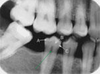

What type of bone is represented in this picture?

Cortical Bone

What type of bone is represented in this picture?

Cancellous Bone